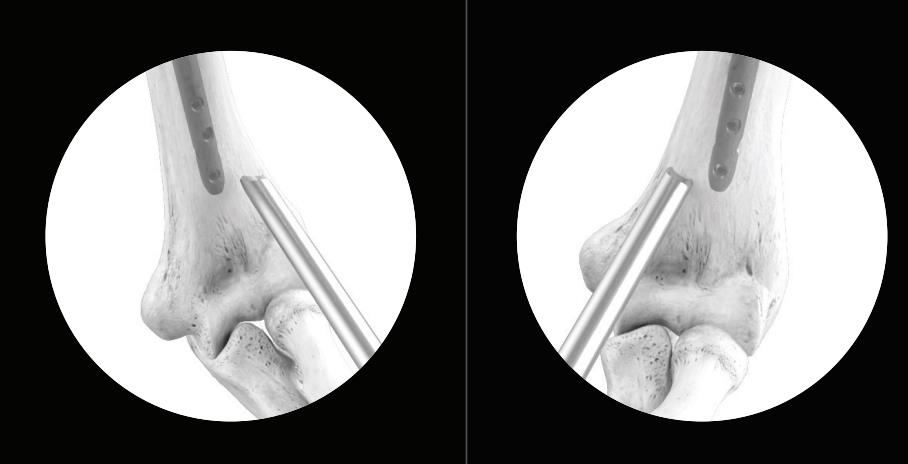

• Distal freehand locking (long nail)

• the freehand drill is held at an oblique angle to the center of the locking hole

• upon X-Ray verification, the drill is placed perpendicular to the nail and drilled through the near cortex

• confirm these views in both the A/P and M/L planes with X-Ray

• after drilling both cortices, the screw length may be read directly off of the Screw Scale

• alternatively, the Depth Gauge can be used to determine the screw length

• the position of the end of the drill is equal to the end of the screw as they relate to the far cortex

• routine Locking Screw insertion is employed with the assembled Short Screwdriver Bit and the Delta Handle

• the self-retaining screwdriver assembly may be used to facilitate freehand locking